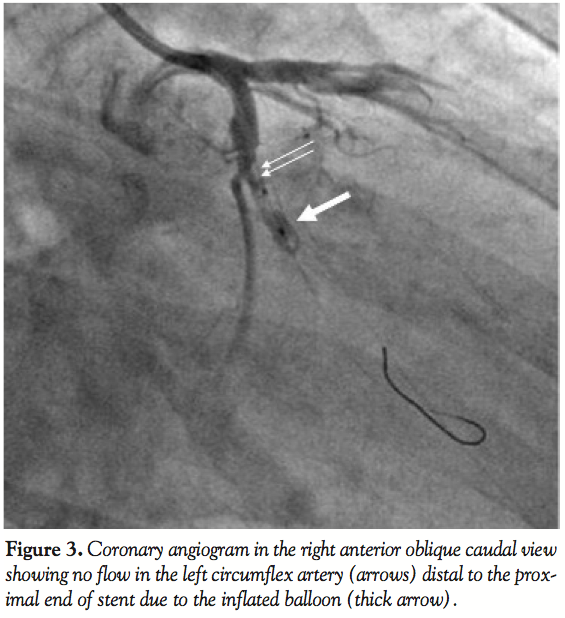

wire (Cordis Corporation, Miami Lakes, Florida) and predilated with a 2.5 x 10 mm Firestar balloon (Cordis Corporation). Residual stenosis was treated with a 3.5 x 13 mm Pronova drug-eluting stent (Vascular Concepts, Bangalore, India). Following stent deployment, incomplete expansion was noted in the mid-portion of the stent. A new 3.5 x 10 mm Firestar balloon (Cordis Corporation) was prepared and placed in the stented segment of the artery for in-stent dilatation. On attempting to inflate the balloon, we realized that the balloon was inflating predominantly in its distal portion (Figure 2). Thus, a negative suction was applied on the balloon catheter to deflate it. However, the distal portion of the balloon did not deflate. We tried to repeat the inflation and deflation of the balloon multiple times after diluting the contrast in the inflation device, but the balloon failed to deflate. Gentle traction was given on the shaft of the balloon while maintaining the negative suction, thinking that the partially inflated balloon might come out. While traction was applied, there was no movement of the balloon within the stent. Subsequently, the shaft of the balloon came out, while the partially inflated balloon was at its original position within the stent. This confirmed that the shaft of the balloon catheter had broken. The patient developed severe chest pain with ST-segment elevation along with hypotension. Angiogram revealed an occluded LCX starting at the inlet of the stent (Figure 3). The LAD also showed TIMI-2 flow. We quickly wired the LAD to maintain the access, anticipating a later thrombogenic complication in the same. An additional 2,500 U of unfractionated heparin were also given. The cardiac surgery team was alerted and surgical retrieval of the entrapped system was planned. In the meantime, a Whisper wire (Abbott Vascular International, BVBA, Belgium) was maneuvered through the stent with difficulty and positioned in the distal artery (Figure 4). Anticipating that a sufficient length of the shaft of broken balloon had been retained inside and was extending into the GC, a 2.5 x 9 mm Maverick balloon (Boston Scientific, Natick, Massachusetts) was advanced over the second wire and positioned near the tip of the GC and inflated to 14 atm so that the proximal part of the broken balloon shaft was trapped between the outer wall of the inflated balloon and inner wall of the GC. A gentle attempt to withdraw the assembly failed to show any movement of the assembly. The balloon was quickly withdrawn. A 2 x 9 mm Maverick balloon was negotiated with great difficulty through the stent on the second wire alongside the partially inflated broken balloon (Figure 4). The balloon was quickly inflated to 5 atm and withdrawn to position it just